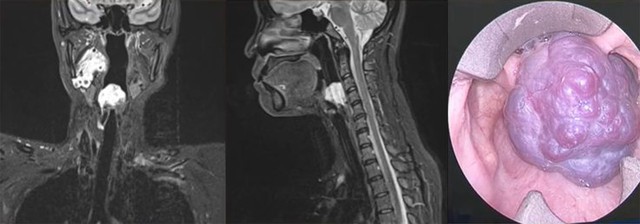

Ca bệnh được ThS.BS.CKII Nguyễn Trương Khương trình bày tại hội nghị là một trường hợp u máu lớn chiếm toàn bộ lòng thanh quản, gây khó thở và vướng khi nuốt – những triệu chứng dễ nhầm lẫn với các bệnh lý thông thường của đường hô hấp trên.

Hình ảnh khối u máu chiếm trọn thanh môn, không thấy cuốn và dây thanh

“Đây là một trong những ca phẫu thuật khó và hiếm gặp, khi ranh giới giữa đường thở và lưỡi dao chỉ cách nhau vài milimét, đặc biệt khi người bệnh lại có tiền căn thay van tim và dùng thuốc chống đông. Chỉ một sai sót nhỏ cũng có thể gây chảy máu nghiêm trọng và đe dọa tính mạng. Vì vậy, ca mổ đòi hỏi sự chuẩn bị kỹ lưỡng, tính toán chính xác từng thao tác và phối hợp nhịp nhàng giữa các chuyên khoa” – BS Khương chia sẻ.

Trước phẫu thuật, người bệnh được ngưng thuốc chống đông 5 ngày và mở khí quản chủ động để đảm bảo an toàn đường thở. Suốt nhiều giờ phẫu thuật, bác sĩ Khương cùng ê-kíp đã sử dụng đốt điện hai cực kết hợp dao siêu âm nhằm cắt triệt để khối u, hạn chế tối đa mất máu và bảo tồn cấu trúc thanh quản.

Sau phẫu thuật, người bệnh hồi phục tốt, chức năng nói, nuốt và hô hấp hoàn toàn bình thường. Kết quả này không chỉ thể hiện trình độ phẫu thuật chính xác, mà còn là minh chứng cho năng lực xử lý những ca bệnh phức tạp của đội ngũ y bác sĩ Bệnh viện ĐKQT Nam Sài Gòn.